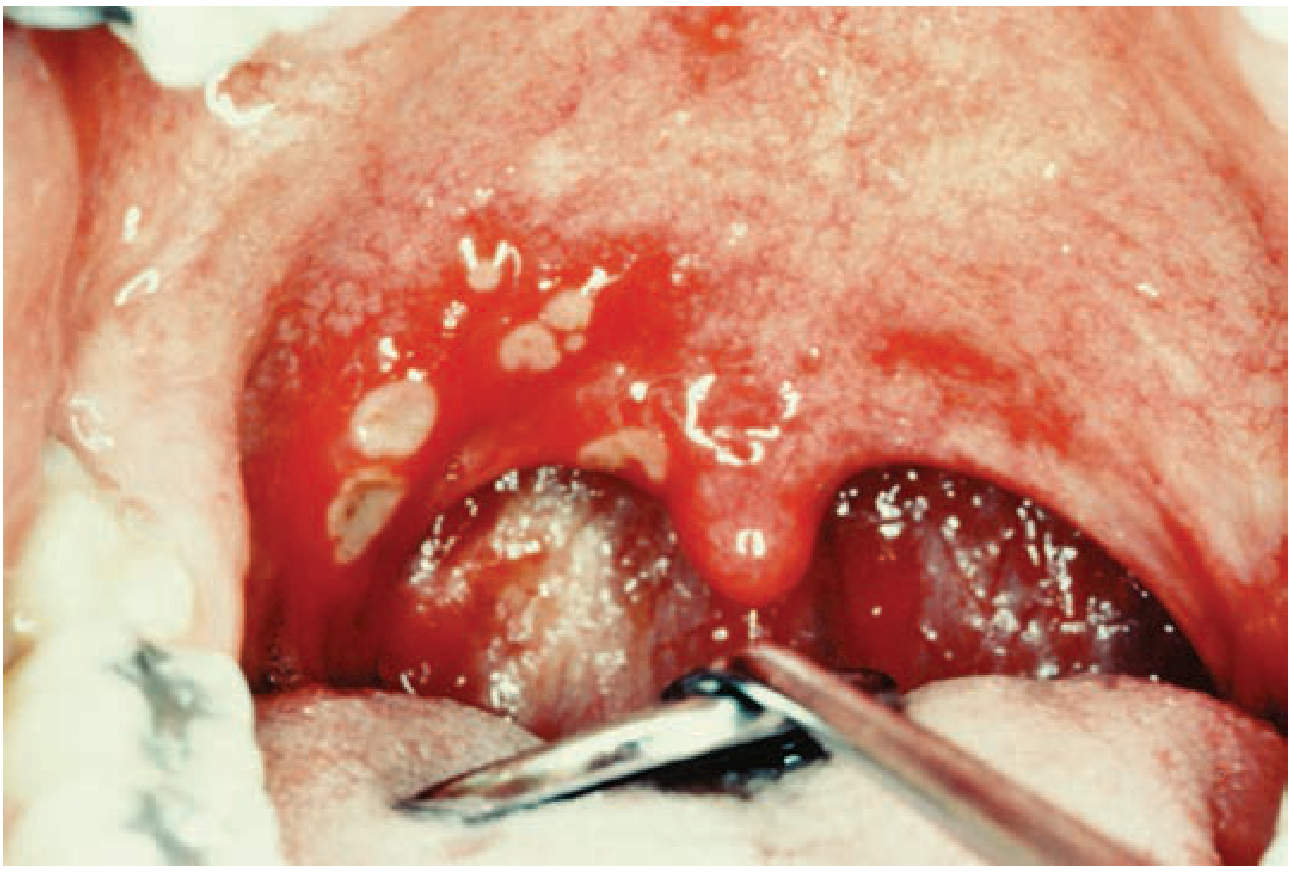

Aphthous stomatitis — multiple painful ulcers on inflamed oral mucosa

Aphthous stomatitis. — Tintinalli's Emergency Medicine